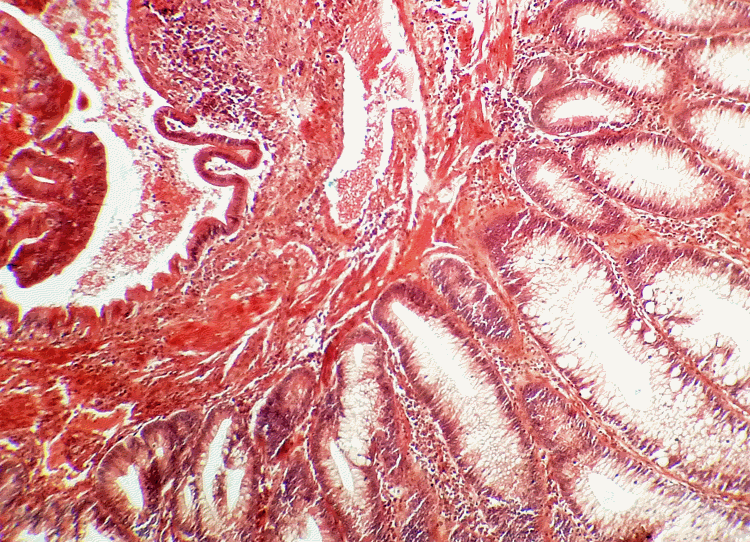

Aujourd'hui, le coffret renferme une collection de coupes histologiques réalisées en 1926 à l'Hôpital Saint Michel à Paris. Nous avons photographié quelques-unes de ces lames portant les fines tranches de tissus biologiques humains préparées à partir de prélèvements sur des patients. Nous ne sommes pas à même de reconnaître les zones médicalement intéressantes et, pour les photographies, nous avons privilégié le jeu des formes et des couleurs : c'est une façon de remarquer la qualité des préparations presque centenaires. Le microscope que nous avons utilisé est plus actuel que l'élégant "Nachet à pied anglais" recommandé, autrefois, pour les travaux d'histologie et de bactériologie. |

| Estomac (Dr V. Pauchet - 1926) | Rectum (Dr R. Duval - 1926) | ||||||||||||||||||||||||||||||||||||||||||||||||||||||||||||||||||||||||||||||||||||||||||||||||||||||||||||||||||||||||||||||||||||||||||||||||||||||||||||||||||||||||||||||||||||||||||||||||||||||||||||||||||||||||||||||||||||||||||||||||||||||||||||||||||||||||||||||||||||||||||||||||||||||||||||||||||||||||||||||||||||||||||||||||

29 mai 1926 - Rectum - Dr Duval, St Michel |

Ces images, qui correspondent à des zones différentes d'une même coupe histologique de doigt, montrent la complexité de la structure des tissus biologiques... |